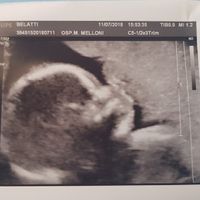

Non mi sembra ancora vero... Aspettiamo un👶

Brigitte, Il 2 Ottobre 2020 alle 20:58

Ciao ragazze, è un po' che non entro più in Community x vari motivi... Ma stasera voglio confidarvi un piccolo, ma stupendo, segreto!!! Dopo un anno di matrimonio e un anno che cerchiamo un bimbo, ho...